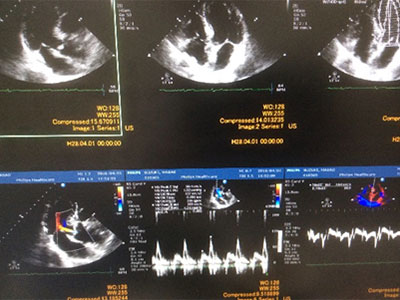

循環器内科

循環器外来のお知らせ

専門医による循環器外来を月1回開設しております。

担当は医療法人永井医院(最上町)の永井俊一医師です。予約制にしておりますので受診希望の方はお知らせください。